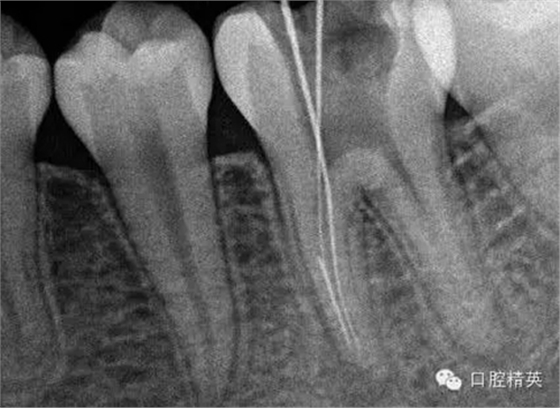

5, 插針確定斷針根管,為近舌根管,插針有阻力,EDTA封存一周復(fù)診。。。

6,打開根管上部通路,根管大量清洗劑等沖洗。。。